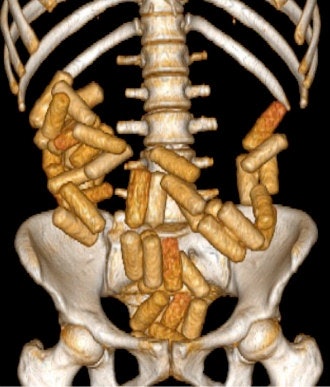

Suspects who are found guilty of acting as drug mules can face long prison sentences so traffickers have developed sophisticated methods to conceal illicit drugs. Body packers carry relatively large packets by swallowing them, so detection of drugs in the gastrointestinal tract by plain film or ultrasound is relatively easy, he added.

In a single trip, a body packer can carry between 50 and100 packages, each containing 8 g to10 g of narcotic agents and weighing up to 1 kg in total. Body pushers, on the other hand, typically carry large packets in the rectum and/or vagina. The packets can usually be detected by physical examination without any need for imaging, but body pushers may also be packers at the same time. A third group known as body stuffers generally possess drugs either for their own use or for dealing on the street. Typically, they hide packets quickly when they encounter the authorities to avoid arrest. Cartels may use children or pregnant women in this capacity.

"Detection of packets filled with liquid cocaine via plain film and ultrasound is more difficult than those filled with solid drugs. Furthermore, drug mules try to disturb exams by rapid breathing or moving. Suspects are also protected against unnecessary examinations and high-dose radiation," noted Bulakçı, who specializes in body imaging and nonvascular interventional radiology. "Studies show that nonenhanced CT can yield 100% success rates for the detection of solid and liquid drugs. That said, the efficacy of CT in body stuffers is not yet clear as there are just a few papers on this issue."

In each radiological examination method, it is important to know how packets containing different materials can be visualized. For example, liquid cocaine is radiopaque with thin lucent lines on plain film, and on ultrasound has a hyperechoic irregular surface with clean shadow. However, on CT it appears hyperdense with thin hypodense lines and a specific jigsaw pattern.